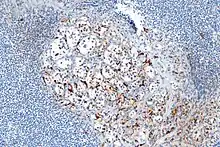

- About 40% of carcinoids have a scattering of sustentacular cells, which stain positive for S-100.[6]